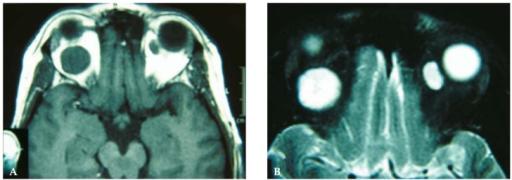

- CT: 골 침범, 석회화 평가

- MRI: 연조직 해상도 우수, 시신경 침범 평가

주요 안와종양 영상 소견